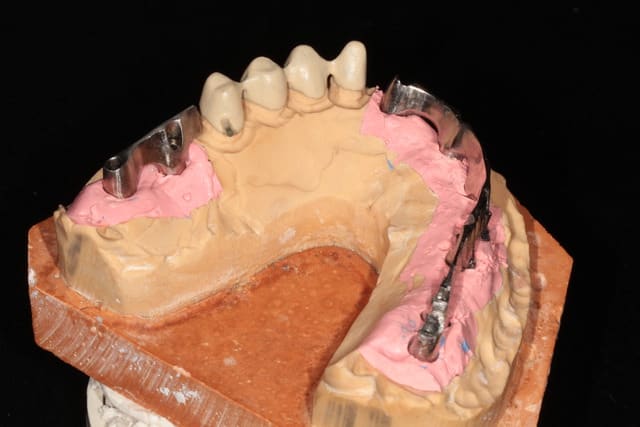

c'est décidé pour la prothèse,chapes soudées sur les 4 dents restantes et barre sur les implants.

je vais faire un essai de fausse gencive céramique avec dents résine....

et maintenant